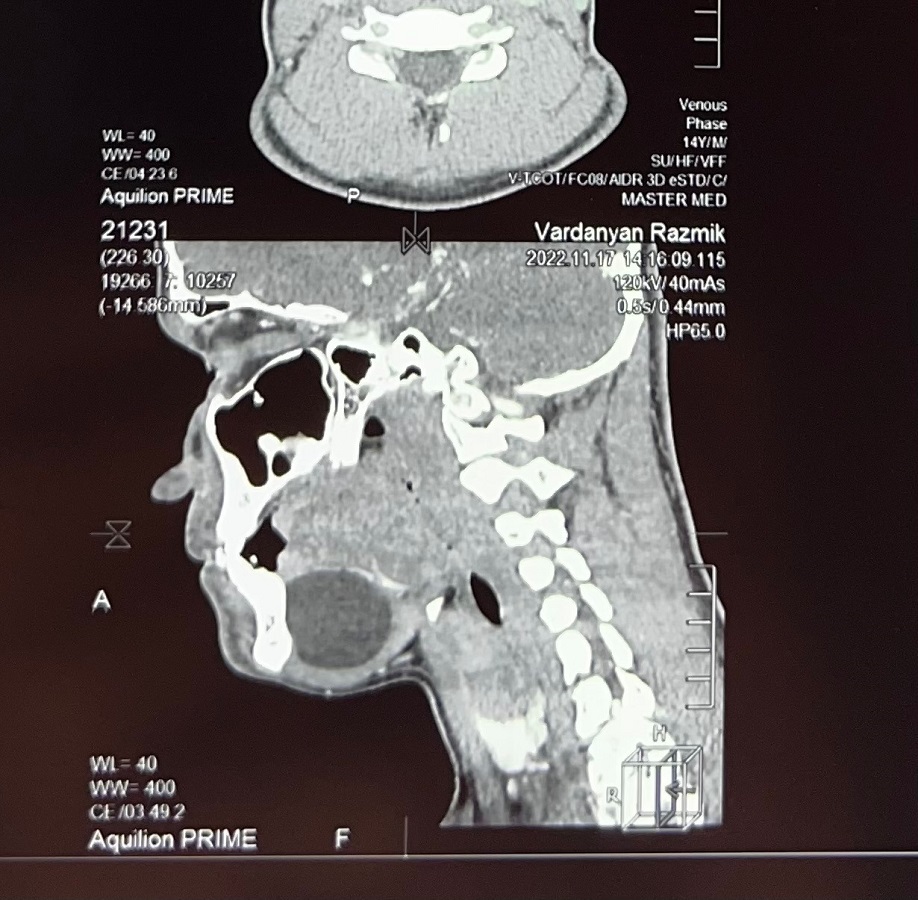

Դիմել են «Մուրացան» համալսարանական հիվանդանոց, կատարված հետազոտությունների արդյունքում ախտորոշվել է պարանոցի միջային հատվածի գոյացություն՝ դերմոիդ բուշտ: